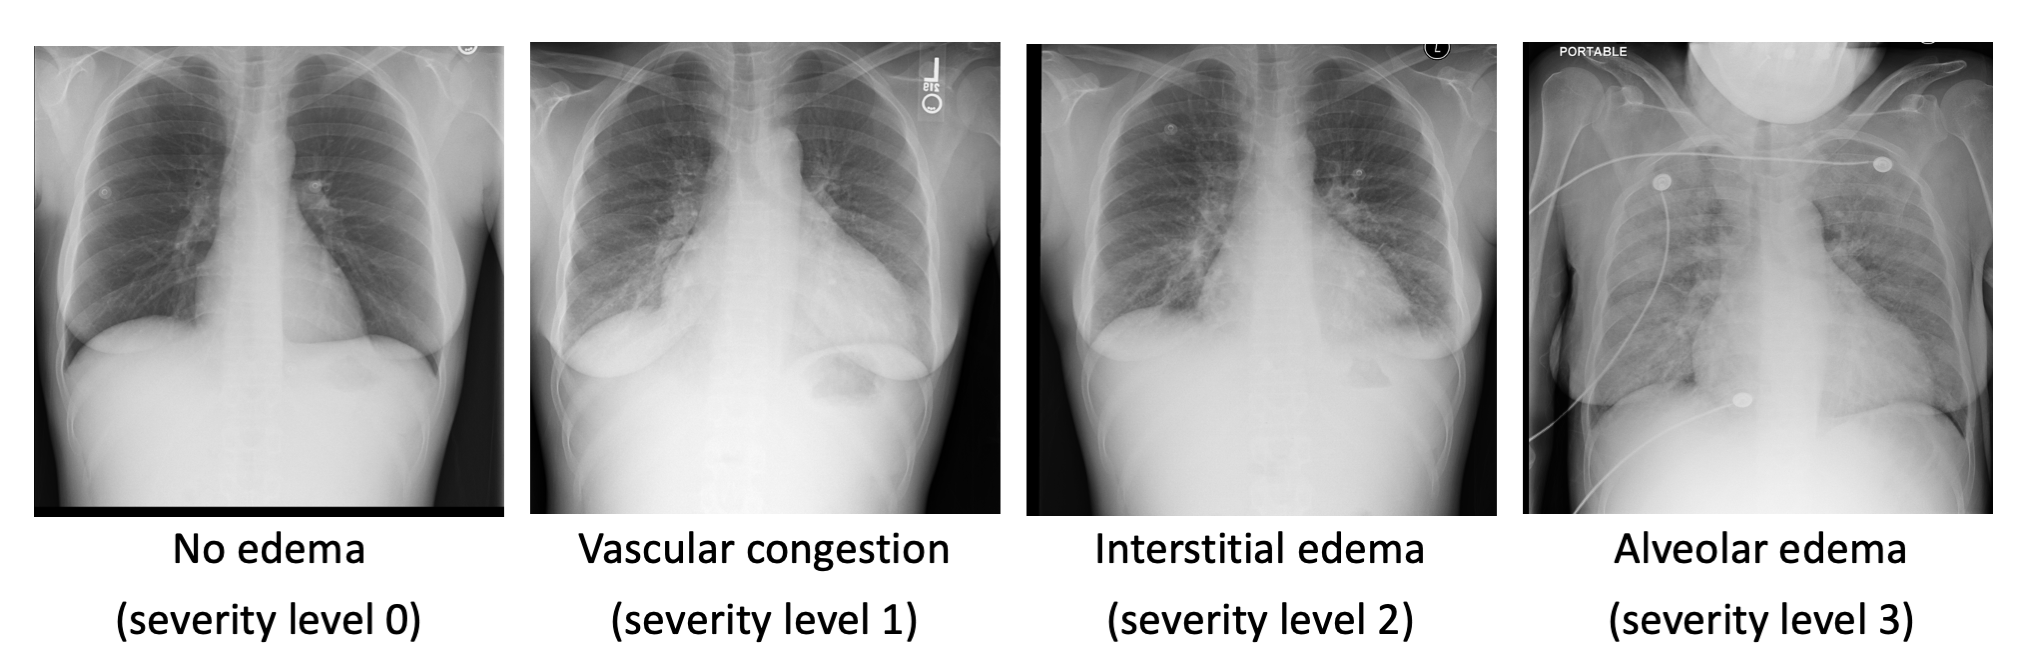

Representative chest x-ray images of pulmonary edema: